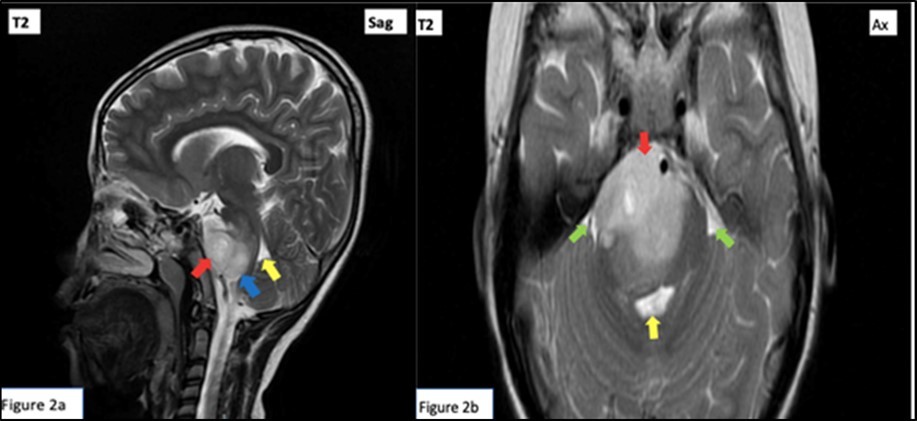

Red arrow: Peripherally enhancing 2.6 x 4.1 x 2.8 cm lobulated mass centered on the right tegmentum of the pons, exhibiting hyperintensity (and hypointensity in T1 weighted images, not shown). Mass renders the pons enlarged and displaces the rest of the pontine parenchyma peripherally. Green arrow: Effacement of bilateral cerebellopontine angle. Yellow arrow: Mild compression on the 4th ventricle. Blue arrow: Small similar looking lesions at medulla oblongata. (Figure 1, Figure 2)

Figure 2.T2 Weighted cranial magnetic resonance imaging sagittal (a) and axial (b) cuts.